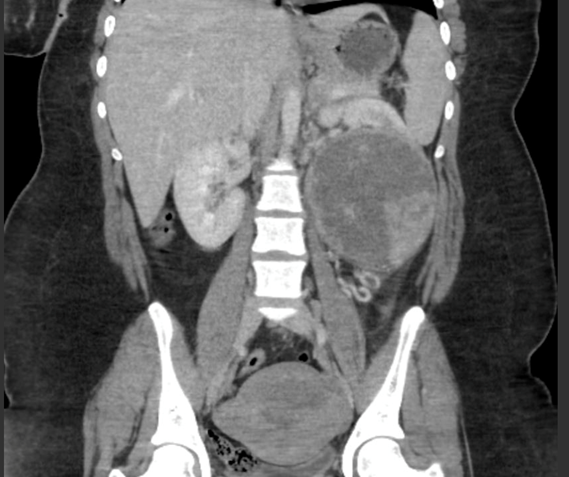

The appearance of the renal mass on CT was highly concerning for malignancy, but we did elect to obtain a biopsy of the mass to inform management. Given her young age we wanted to ensure that this was not a rare subtype, including medullary or collecting duct cancer, that may benefit from neoadjuvant therapy or immediate treatment. Additionally, there was the possibility of a benign mass that could be observed for the whole duration of pregnancy. Our patient’s biopsy findings of “oncocytic renal neoplasm” suggested chromophobe RCC or possibly oncocytoma (although pathology leaned away from benign pathology). Untreated large renal masses (>4cm) show ~1% risk of metastatic spread per year, but chromophobe RCC has lower malignant potential than other subtypes, ev heterogeneous en for larger masses.6 The biopsy results supported holding off on surgery until at least the second trimester when anesthetic risk to organogenesis decreases, and we did discuss the possibility of delaying surgical intervention until after delivery Figure 1.

Figure 1 Coronal noncontrast CT showing a heterogeneous mass in the left kidney.

Ultimately, the additional concern for rupture along with malignant potential moved us to surgical intervention during her pregnancy. The mass had demonstrated a 25% decrease in size from 12.8cm when first diagnosed at full term during her initial singleton pregnancy to its next measure 9.5cm at 8 weeks of her twin pregnancy. Plasma volume in a singleton pregnancy rises approximately 50% above non-pregnant baseline normal during the last trimester and likely accounted for this fluctuation in size. However, in twin pregnancy, plasma volume can rise to 67% above baseline.7 The intra-abdominal pressures from the large vascular renal mass and fully gravid twin uterus–particularly during labor–raised our concern for possible rupture of the mass (and consequent upstaging for malignancy). Additionally, she could develop persistent, severe hypertension, as she displayed during her first pregnancy, further increasing risk of rupture. It was due to these considerations that we elected to proceed with nephrectomy at the start of her second trimester before her uterus became significantly enlarged.